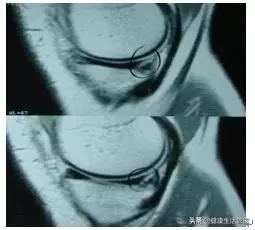

(正常半月板)

(撕裂的半月板)

核磁共振是诊断半月板损伤、韧带撕裂准确率最高的影像学检查手段,根据核磁共振可将半月板损伤分为4级,(0级:正常半月板,呈“黑三角形”,边缘锐;I级:半月板内可见不规则信号,没有波及半月板关节面;II级:半月板内线状信号,没有波及半月板关节面,但可延伸到半月板关节囊结合部;III级:半月板内信号波及半月板表面,提示半月板撕裂;VI级:半月板毁损)。

Ⅲ级撕裂